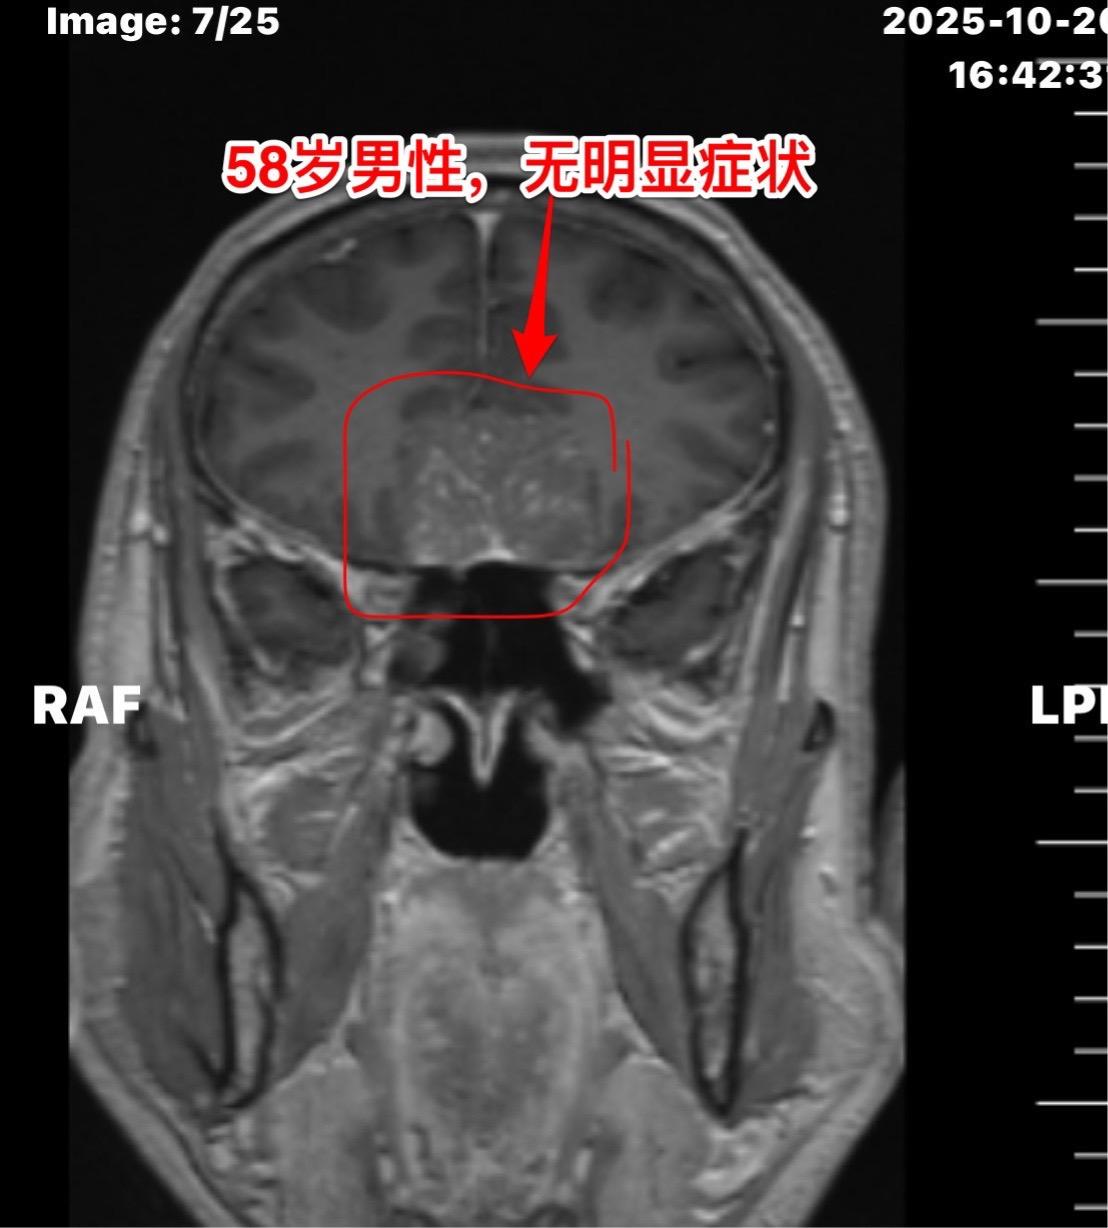

这个是脑膜瘤吗?58岁男性,洛阳市人。今年10月份单位作体检,发现这个瘤。病人无明显症状,无头痛,无视力下降。 是脑膜瘤吗? 脑膜瘤是脑部发病率最高的原发肿瘤,绝大多数脑膜瘤是良性肿瘤,不是所有的脑膜瘤都需要作手术。